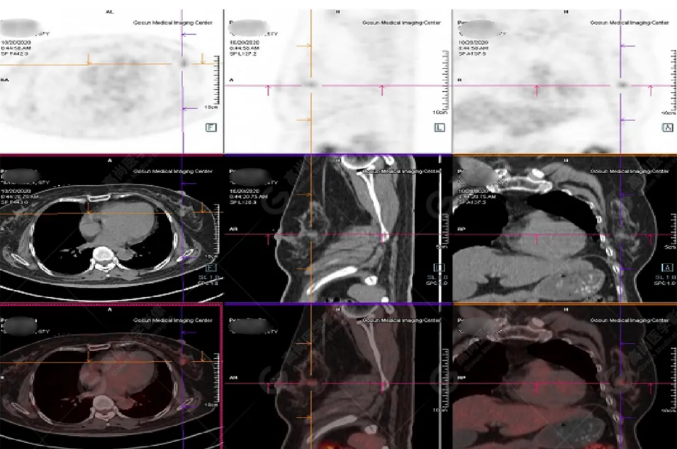

病史摘要:女性 36歲 因左后肋區(qū)疼痛1月余查體,無(wú)其他不適。PET/CT影像圖

左胸一后肋溶骨性骨質(zhì)破壞,周圍伴軟組織形成,F(xiàn)DG代謝增高,SUVmax為10.9。

找到引起骨痛病灶,病因:原發(fā)?轉(zhuǎn)移?感染?

最終診斷:宮頸癌伴肋骨單發(fā)骨轉(zhuǎn)移。